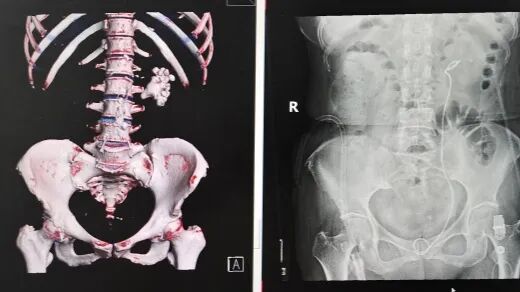

患者鄭奶奶因突發(fā)腰痛前往醫(yī)院就診,經(jīng)CT檢查結(jié)果顯示,其左腎已被結(jié)石完全填充,確診為典型的腎鑄型結(jié)石。腎鑄型結(jié)石因形態(tài)酷似鹿角,又被稱(chēng)為鹿角形結(jié)石,這類(lèi)結(jié)石會(huì)在腎臟內(nèi)長(zhǎng)期生長(zhǎng),逐漸填滿(mǎn)腎臟內(nèi)部空間形成整體形態(tài)結(jié)石,不僅治療處理難度極大,還伴隨極高的感染風(fēng)險(xiǎn)。

針對(duì)鄭奶奶這一復(fù)雜病例,常規(guī)手術(shù)方式通常需分次操作,且要在腎臟上人為開(kāi)鑿多個(gè)孔洞,將結(jié)石分塊擊碎后再逐一取出。這種傳統(tǒng)手術(shù)方式不僅會(huì)對(duì)患者身體造成較大創(chuàng)傷,還會(huì)延長(zhǎng)術(shù)后恢復(fù)時(shí)間。為最大程度減輕患者痛苦,保障手術(shù)安全與效果,泌尿外科博士團(tuán)隊(duì)在術(shù)前展開(kāi)周密準(zhǔn)備工作:通過(guò)詳細(xì)檢查充分評(píng)估結(jié)石分布范圍、大小形態(tài)及腎內(nèi)結(jié)構(gòu)情況,反復(fù)研討制定出科學(xué)周密的個(gè)性化手術(shù)方案。

手術(shù)當(dāng)天,科室副主任喻衛(wèi)東及手術(shù)團(tuán)隊(duì)在超聲精準(zhǔn)引導(dǎo)下,為患者建立起一個(gè)僅筷子粗細(xì)的微創(chuàng)小隧道,直達(dá)腎臟內(nèi)結(jié)石位置。隨后,利用醫(yī)院最新引進(jìn)的高效率碎石設(shè)備——?dú)鈮簭椀浪槭瘷C(jī),將腎盂內(nèi)的結(jié)石逐一擊碎并吸出。在手術(shù)過(guò)程中,面對(duì)部分藏于腎臟角落的細(xì)小結(jié)石,喻衛(wèi)東創(chuàng)新性地采用可彎曲軟鏡,靈活調(diào)整軟鏡角度,巧妙 “拐進(jìn)” 腎臟角落,耐心將隱藏結(jié)石勾出至視野清晰區(qū)域后,再進(jìn)行精準(zhǔn)擊碎處理。經(jīng)過(guò)團(tuán)隊(duì)的不懈努力,最終在僅保留單一微創(chuàng)通道的前提下,實(shí)現(xiàn)了腎臟內(nèi)結(jié)石的 “無(wú)死角” 清理。術(shù)后,鄭奶奶生命體征平穩(wěn),恢復(fù)狀況良好。